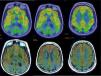

Dementia is a syndrome characterised by chronic, multi-domain, acquired cognitive impairment that causes significant functional limitations. MRI is the standard imaging study for these cases, since it enables detection of the atrophy patterns of the various neurodegenerative diseases (Alzheimer's disease, frontotemporal degeneration, Lewy body dementia), the vascular lesions associated with vascular dementia, and various potentially reversible diseases (for example, tumours, hydrocephaly) or diseases that require special management measures (for example, prion diseases). In certain cases other imaging methods can be used, such as CT, functional MRI, HMPAO SPECT or dopaminergic markers and FDG PET, amyloid markers or dopaminergic markers. The indications for these methods have not yet been clearly established, and therefore should be used in multidisciplinary dementia units.